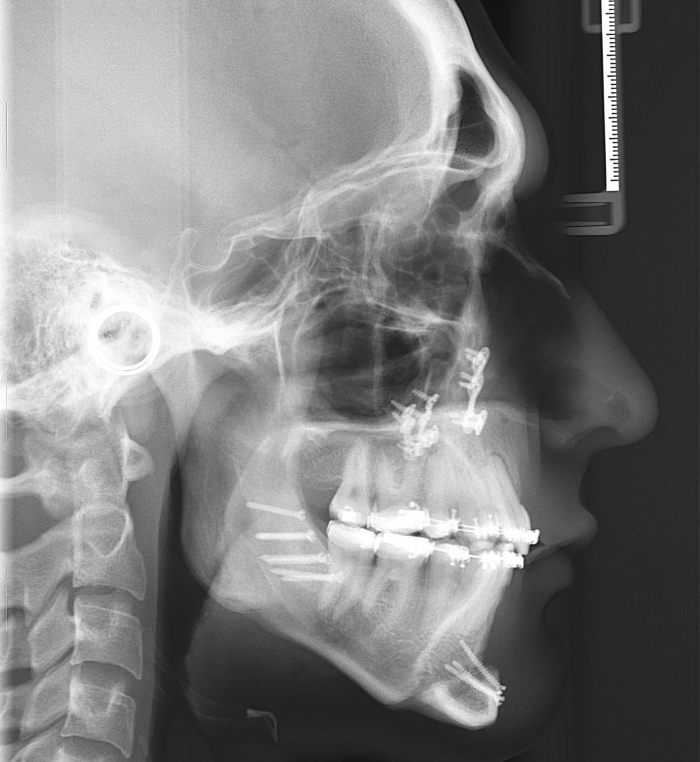

Telerradiografia inicial